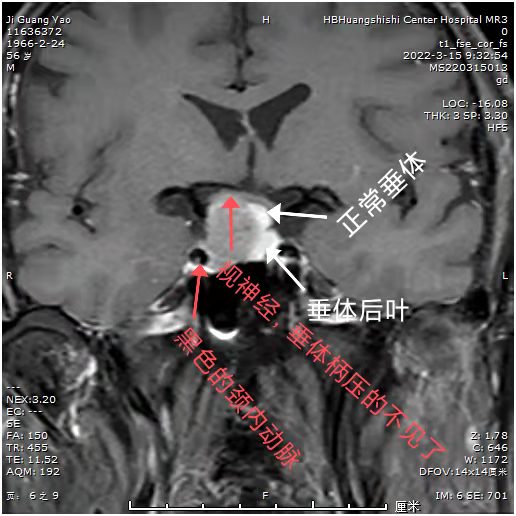

患者近期视力明显下降,一侧视力只有0.1,而且感觉眼部肿胀不适。MRI:发现鞍区占位。常规CTA,发现鞍区小动脉瘤!如果先处理动脉瘤,介入需支架辅助,术后需口服抗凝药物,近期3个月内,不能手术。患者必将失明!怎么办?和患者及科室血管介入组沟通后,患者意愿强烈,先行垂体瘤手术,做好术中动脉瘤破裂可能,带上动脉瘤夹,备用。

可见动脉瘤和垂体瘤很近

术后显示肿瘤切除满意,正常垂体及垂体后叶后叶保留,术后患者诉视力明显改善。眼睛暴胀感消失。视力基本正常范围。